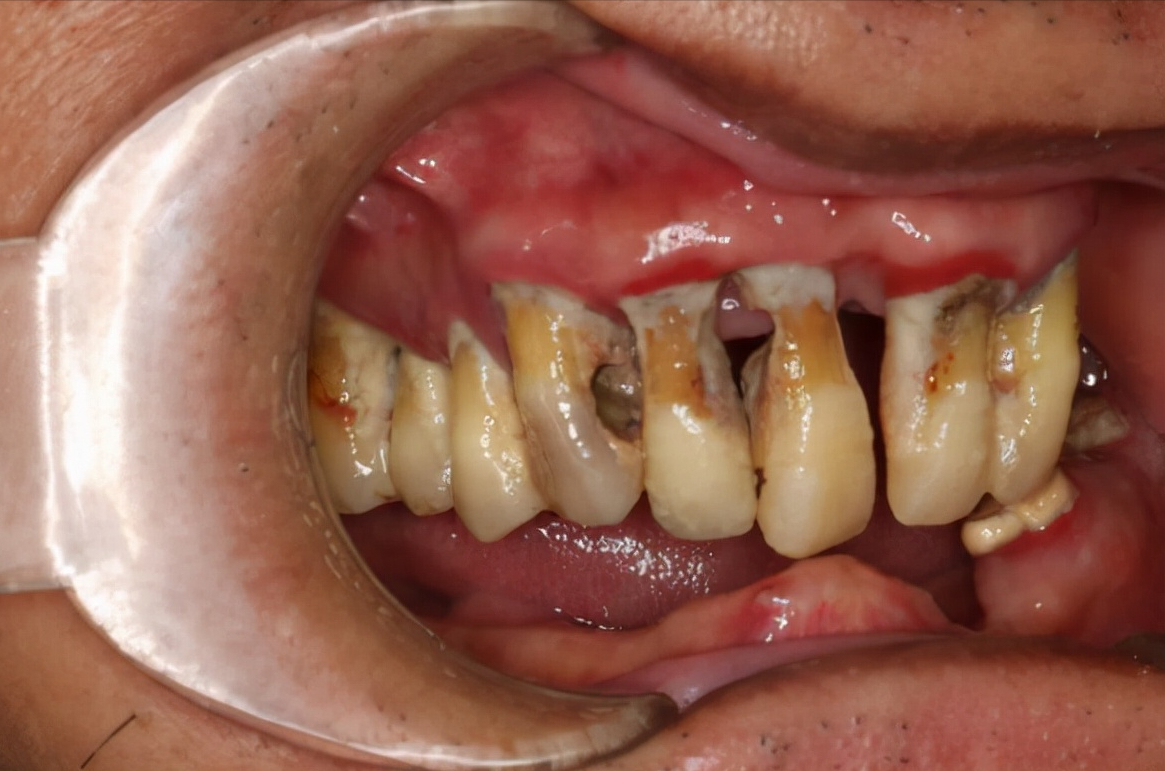

第一次,我踏进口腔医院,第一次,知道为什么牙龈出血和口臭伴随了我这么多年,是因为牙结石。

她说,牙结石就是刷牙没刷走遗留下的细菌团块,它紧紧附着在牙齿和牙龈之间,开始是软垢,慢慢就积累变硬,终变成牙结石。

医生拿了个模型,告诉我:牙齿和牙龈本应该紧紧贴在一起,但因为牙结石他们被迫分开,牙结石上的细菌还不断刺激牙龈,终导致牙龈发炎,红肿出血,这种情况下刷牙牙龈会疼,疼就不敢用力去刷,不刷牙龈会更肿,形成了一个恶性循环。

牙结石是由陈年的细菌堆积而成的,细菌在嘴巴里面一直发酵,当然会有味道。

牙结石还分为龈上牙结石和龈下牙结石,龈上牙结石就是我们肉眼能看得到的那些黄黄的像水垢一样的东西,而龈下牙结石却是隐藏在我们的牙龈下面,牙龈出血、口臭、牙龈发黑的元凶就是它!

龈下牙结石就像一个霸道又无理的侵略者,它紧紧地贴着我们的牙齿悄悄向下蔓延,包裹住我们的牙根,如果你一直不去处理这些“坏东西”,发展成牙周病,骨头吸收,牙齿松动是早晚的事。